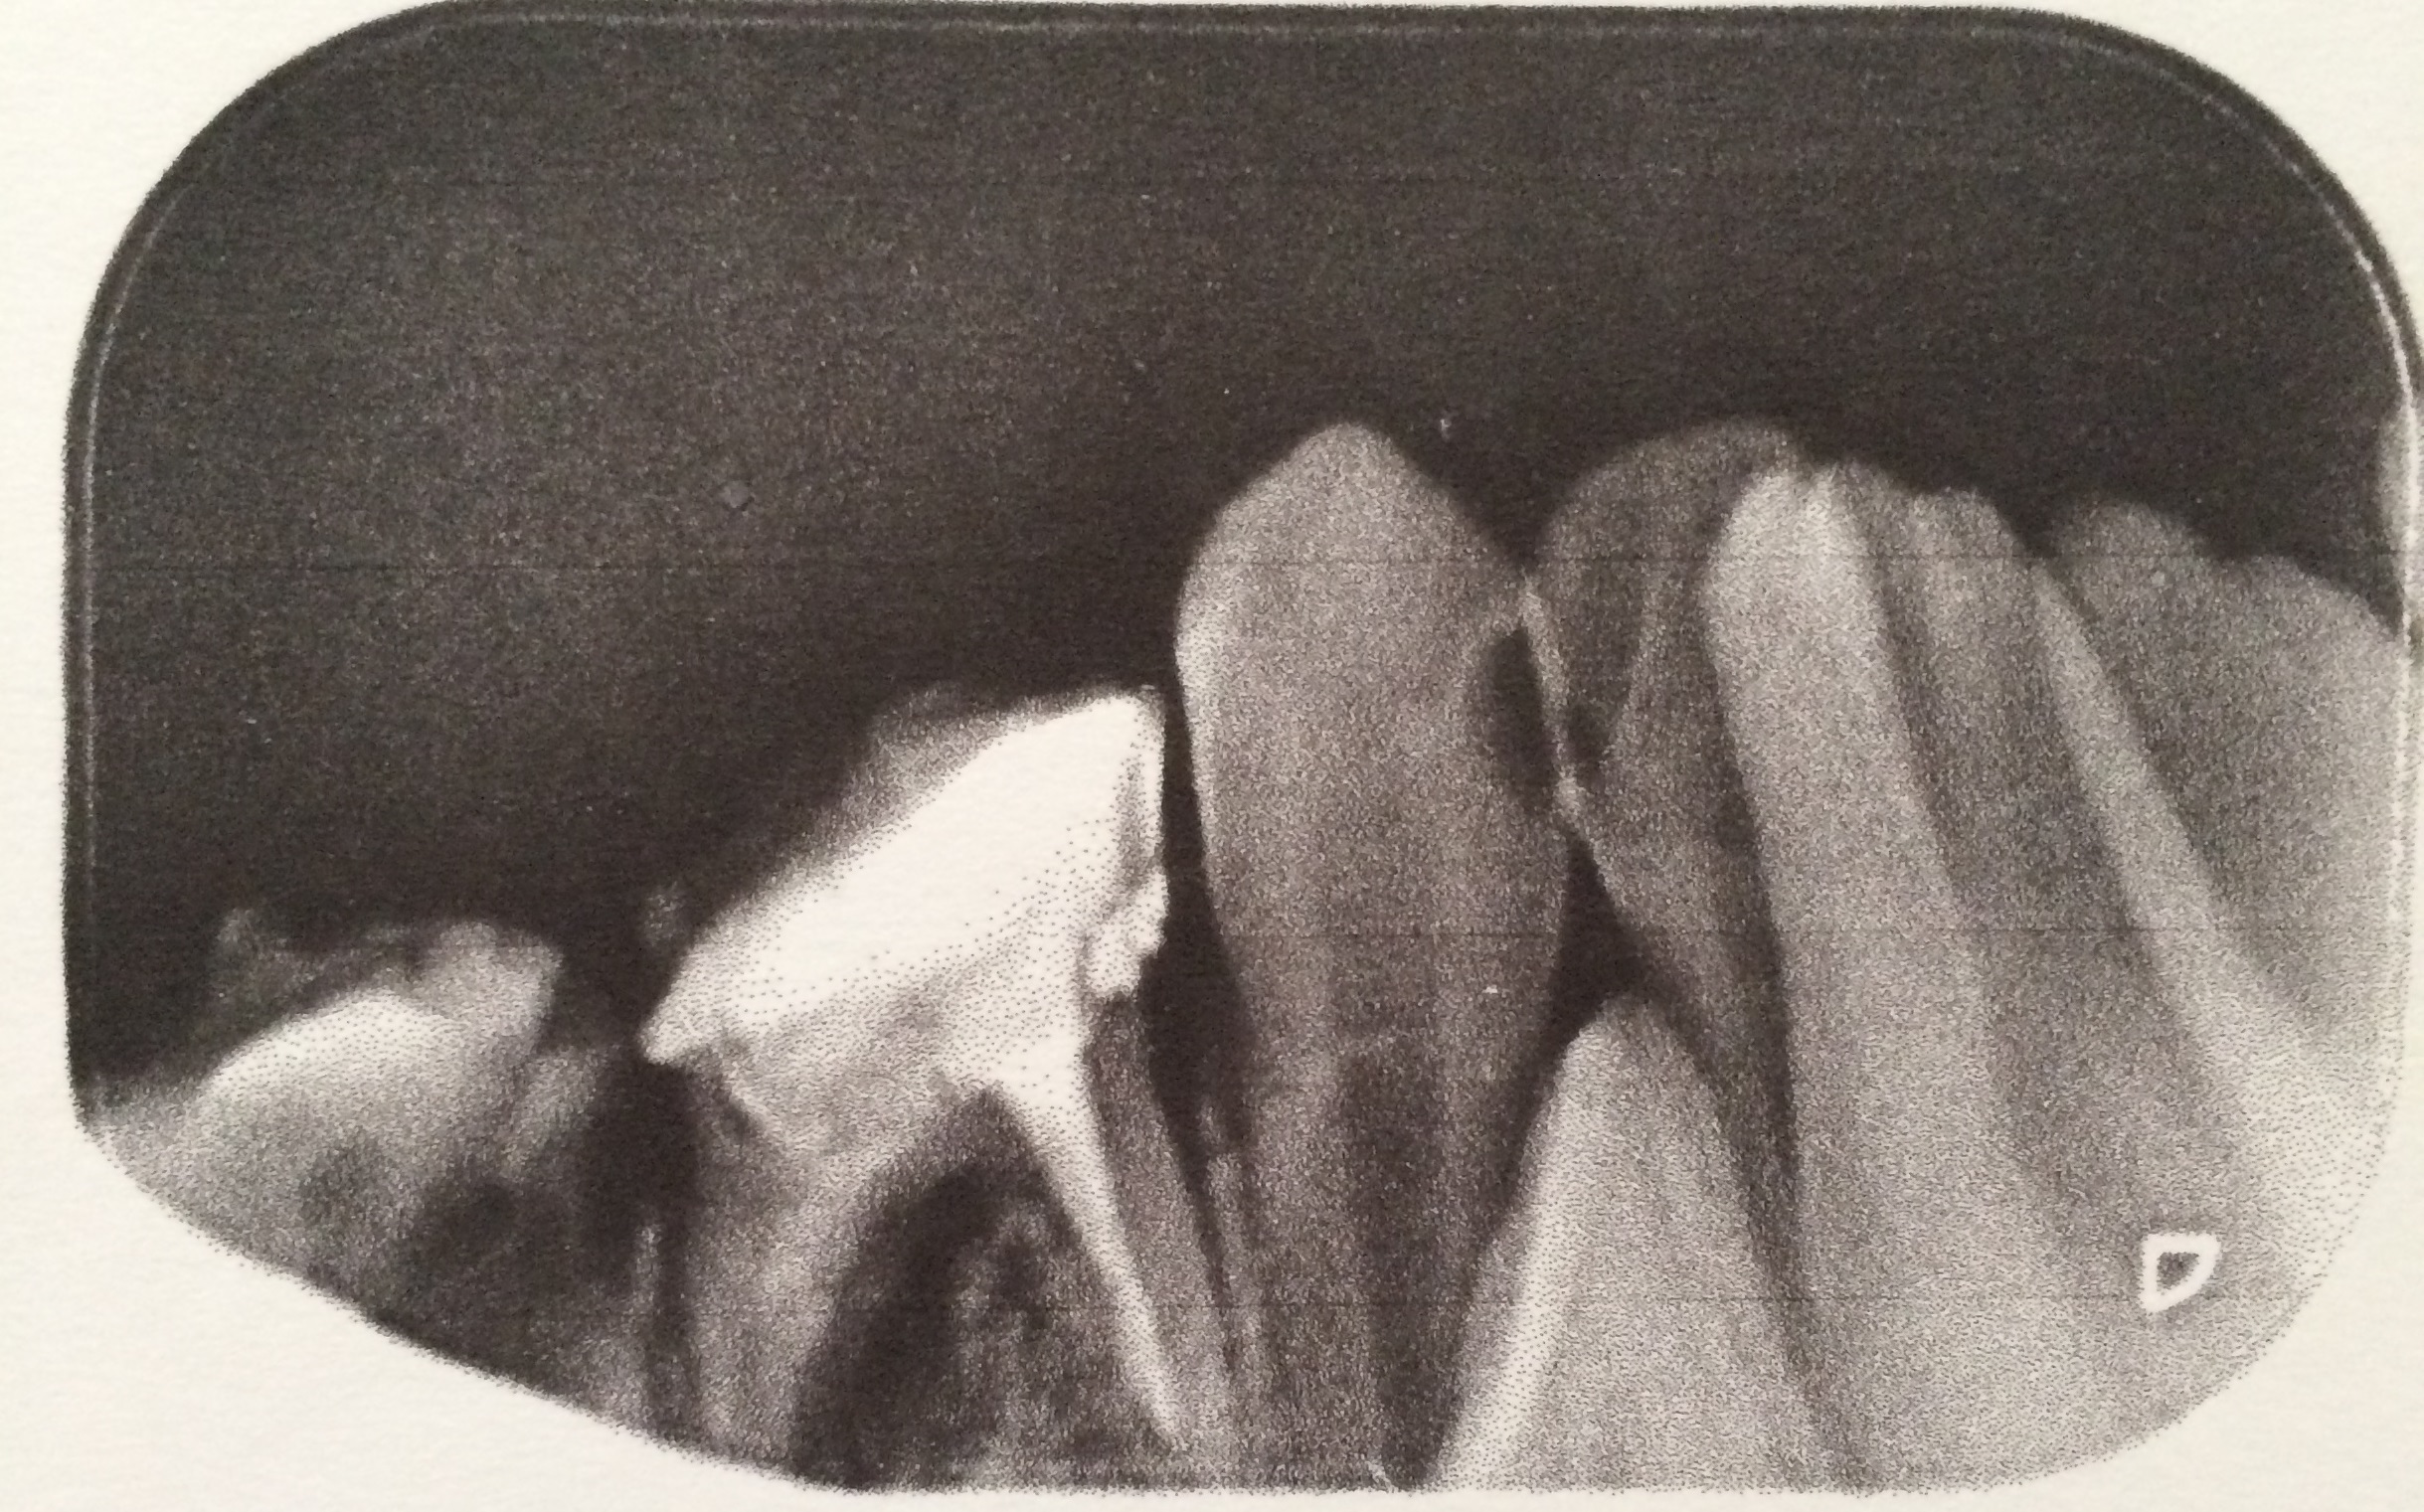

Perforasi iatrogenik merupakan salah satu resiko yang sering terjadi dalam perawatan endodontik yang disebabkan oleh kesalahan operator. Perforasi dapat terjadi pada apeks, lateral atau korona. Perawatan untuk perforasi dapat dilakukan dengan bedah atau non bedah. Prognosis dari perforasi endodonti dipengaruhi oleh beberapa faktor antara lain adalah waktu terjadinya perforasi, lokasi perforasi dan besarnya perforasi. Tujuan laporan kasus ini untuk melaporkan perawatan perforasi korona pada pulpektomi gigi decidui. Kasus seorang anak laki-laki usia 6 tahun datang bersama ibunya dengan keluhan gigi bawah belakang kanan sering sakit tiba-tiba sejak tiga bulan yang lalu. Diagnosis pada gigi molar pertama kanan rahang bawah adalah karies profunda kelas I dengan pulpitis irreversible. Perawatan yang dilakukan adalah pulpektomi. Dalam proses perawatan terjadi perforasi korona di mesial yang disebabkan oleh trauma bur preparasi saat dilakukan pembukaan atap pulpa. Perawatan pulpektomi tetap dilanjutkan dengan menutup daerah perforasi dengan zinc phosphat cement dan diakhiri dengan tumpatan tetap stainless steel crown (SSC). Kesimpulan dari laporan kasus ini yaitu perawatan perforasi korona dengan non bedah pada pulpektomi gigi decidui mempunyai prognosis yang baik. Perawatan dilakukan dengan bahan tumpatan yang memiliki ketahanan terhadap saliva dan tidak mengiritasi pulpa ataupun gingiva.